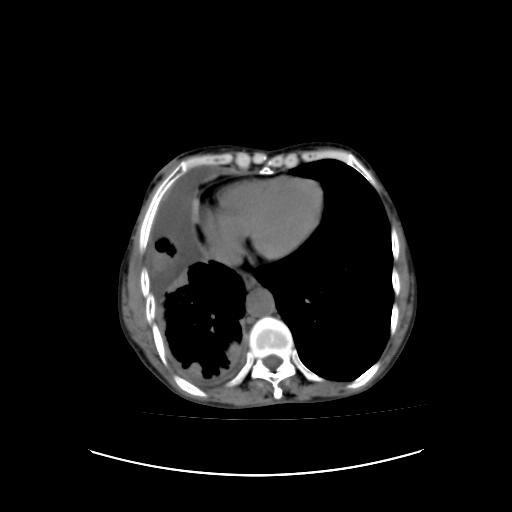

标题: CT16930:女 59 胸痛6个月 胸水脱落细胞学见瘤细胞 [打印本页]

标题: CT16930:女 59 胸痛6个月 胸水脱落细胞学见瘤细胞

恶性胸膜间皮瘤伴肺内转移可能性大;或胸膜、肺内均为转移瘤,左肺下叶亦见多发小结节影。

右侧胸廓塌陷,右侧胸膜广泛增厚并见多发胸膜结节,右侧少量胸腔积液并包裹。

胸膜转移瘤  包裹性胸腔积液  肺内转移

右胸腔结节均考虑来自胸膜(部分来源于叶裂),考虑胸膜间皮瘤或转移瘤.